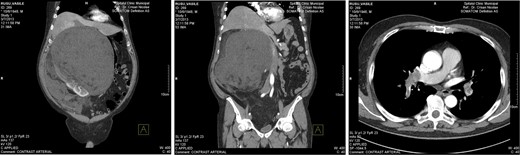

The first is the case of a 65-year-old man without significant personal history who presented to the general practitioner with a progressively distended abdomen associated with weight loss, fatigue and dyspnoea. Abdominal ultrasonography and contrast-enhanced abdominal computed tomography (CT) found a voluminous, mixed-density mass located retroperitoneally in the right perirenal area; the mass was approximately 39 × 39 × 38 cm in size, with clearly defined, irregular margins and a few visible vessels, and was subsequently identified macroscopically as a right renal angiomyolipoma. The mass was in contact with the pancreas (displacing the cephalic and corporeal sides of the pancreas), the stomach (the distal third), the aorta, the liver (the visceral side), the gallbladder, the ascending and transverse colon, the inferior vena cava and the portal vein. The mass occupied the entire right hemi-abdomen, compressing the abdominal organs, displacing the liver cranially above the sixth rib and compressing the large vessels (Fig. 1). Thoracic CT revealed the presence of pulmonary emboli (Fig. 2), for which we initiated specific therapy.

Thoracic and abdominal CT—right perirenal retroperitoneal liposarcoma with massive secondary thromboembolism.